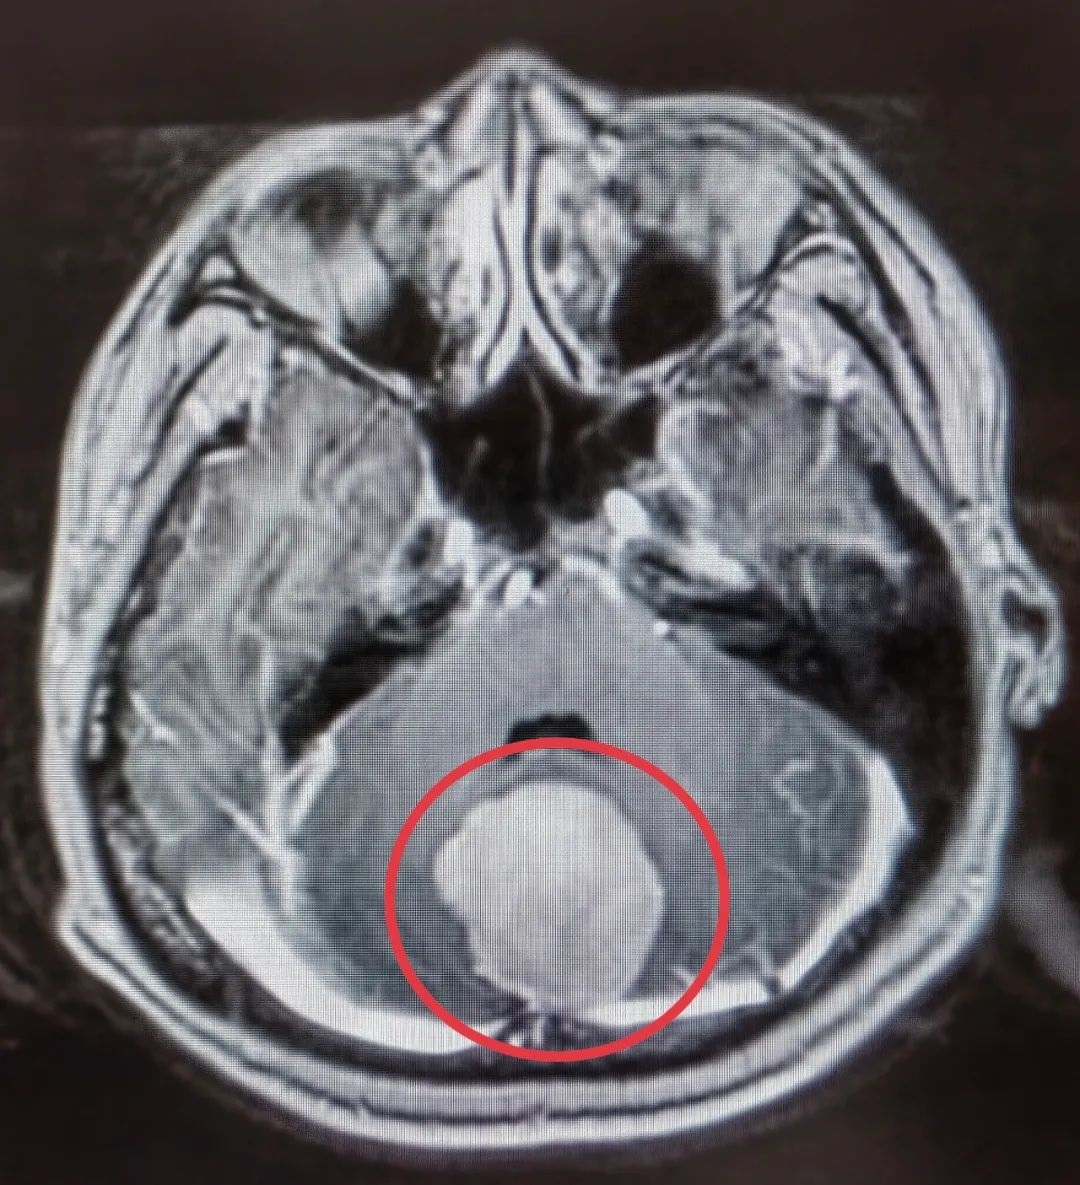

术前头颅MRI提示:窦汇区脑膜瘤,大小约4X3.6X0.3cm

神经外科宋增亮介绍,该脑膜瘤生长位置特殊,位于横窦、窦汇以及直窦交界处,在脑膜瘤中占比小于4%,由于窦汇区是颅内所有的静脉回流血汇合的地方,手术极易大出血,因此这一区域的脑膜瘤手术难度相对比较大。